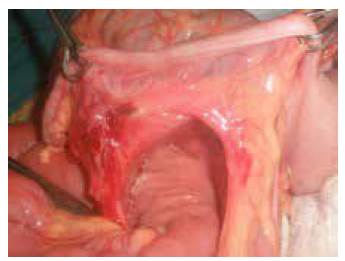

Los hallazgos intraoperatorios fueron hernia paracecal y fibrosis desde el ligamento de Treitz hasta el ciego, que comprometía el mesenterio ileocecal y el apendicular; además, había múltiples adenopatías ileocecales y de yeyuno, ciego móvil y protrusión por el orificio herniario de asas yeyuno-ileales sin compromiso vascular (figuras 1 y 2).

Se liberó el segmento intestinal herniado, se cerró el defecto herniario y se practicó la apendicectomía. No hubo complicaciones durante el posoperatorio inmediato.